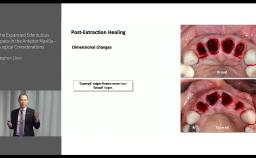

Structured Assessment and Treatment Planning

Post-Extraction Healing – Implications for Implant Treatment and Ridge Maintenance

Congress Lecture